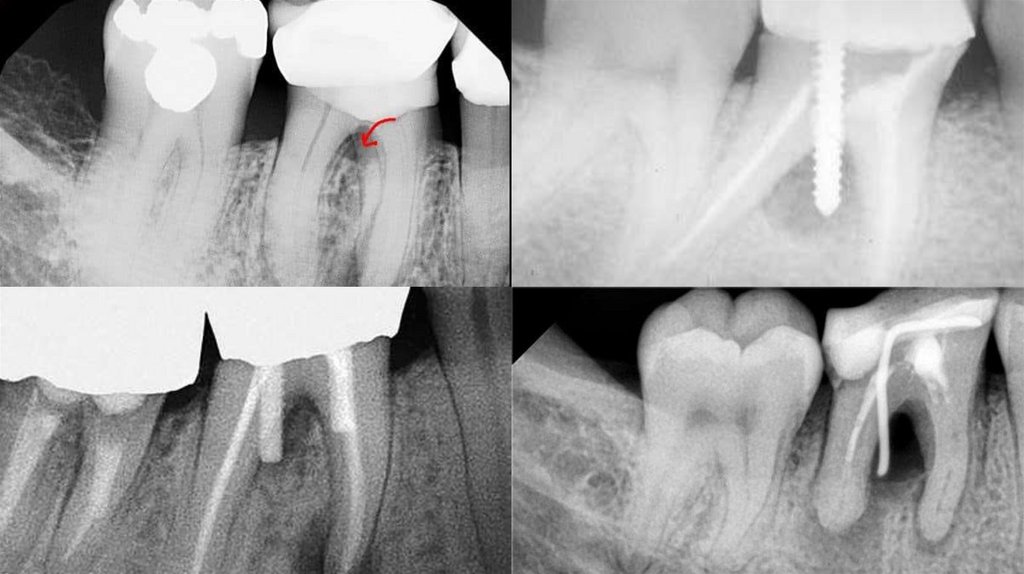

15. Перфорация корневого канала

Закрытие перфорации корня в коронковой трети возможно

двумя способами:

1) пломбируют основной канал с последующим заполнением

перфорации;

2) перекрывают перфорацию материалом, предварительно

введя в

основной канал файл.

19. Профилактика перфораций корня

При обработке сильно изогнутых корневых каналов необходимо соблюдать следующие условия:

1) обязательно предварительное рентгенологическое исследование конфигурации корневых каналов;

2) необходимо придать ручным инструментам изгиб, соответствующий кривизне корня (при этом их направления

должны совпадать);

3) использовать антикурватурную технику прохождения с помощью Safety Hedstroem files (Kerr) — Н-файл с

односторонней гладкой поверхностью рабочей части;

4) для эффективного прохождения узких кальцифицированных корневых каналов применять специальный инструмент

Pathfinder CS (Kerr) из углеродистой стали;

5) использовать гибкие ручные или вращающиеся никель-титановые инструменты с неагрессивной верхушкой;

6) постоянный рентгенологический контроль за прохождением и расширением корневого канала под штифтовые

конструкции или использование апекслокатора